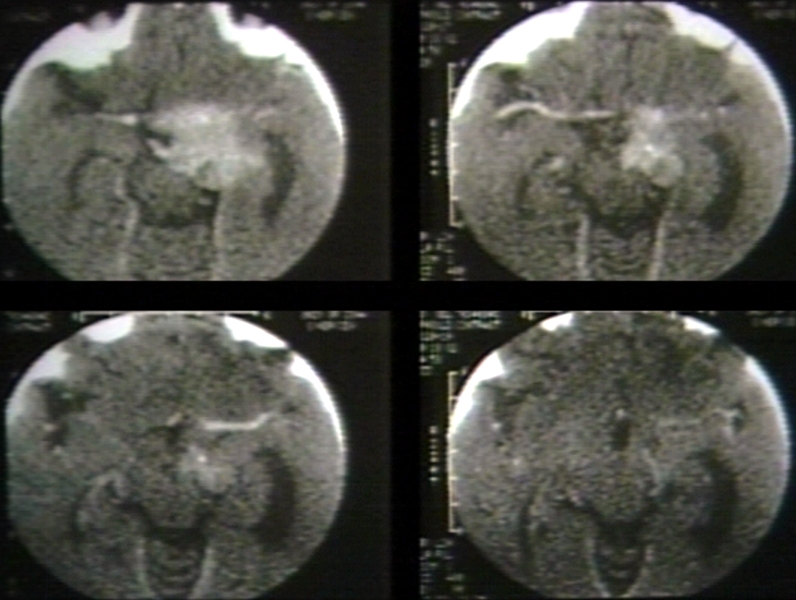

RADIOLOGY: PITUITARY: ADENOMA, PITUITARY; - 4 ON 1 - D (CT)